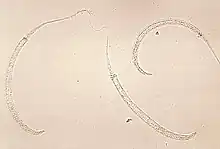

| Photomicrograph of larvae | |